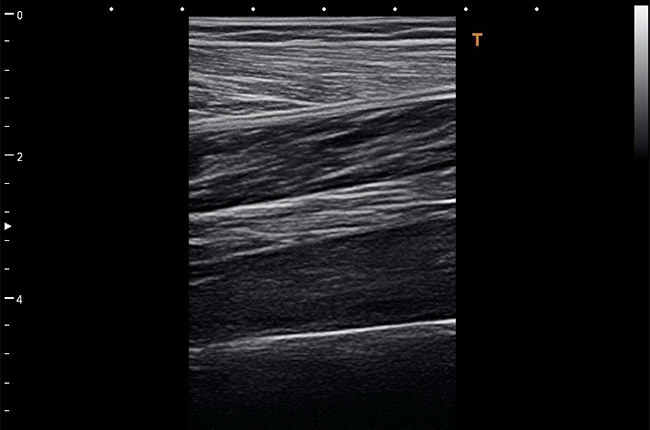

Скелетно-м'язова система